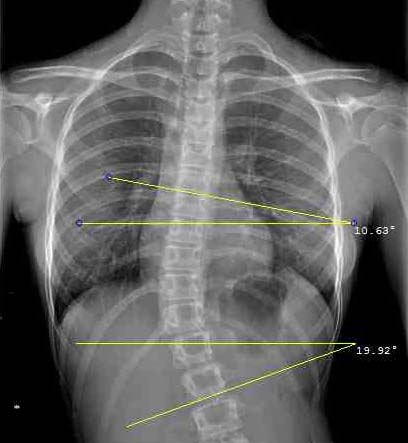

L’inclinometro di D’Osualdo è uno strumento originale che riunisce due importanti funzioni: la misurazione del gibbo (angolo di rotazione del tronco in anteroflessione) nel paziente affetto da scoliosi e la misurazione dell’angolo di Cobb sulle radiografie; in questo caso può essere utilizzato sia nelle curve sul piano frontale (scoliosi) sia nelle curve sul piano sagittale (cifosi e lordosi).

Nella misurazione delle radiografie il bordo dello strumento viene accostato al bordo della vertebra limite superiore della curva, l’asta viene quindi ruotata fino a metterla in bolla; il grado di inclinazione viene letto sulla scala goniometrica; l’operazione viene quindi ripetuta per la vertebra limite inferiore. L’angolo di Cobb è dato dalla somma degli angoli di inclinazione delle due vertebre limite.

L’inclinometro è utile anche per la precisa identificazione sulla radiografia delle vertebre limite che sono appunto le più inclinate.

L’inclinometro è molto utile per individuare rapidamente sulla radiografia le vertebre più inclinate.